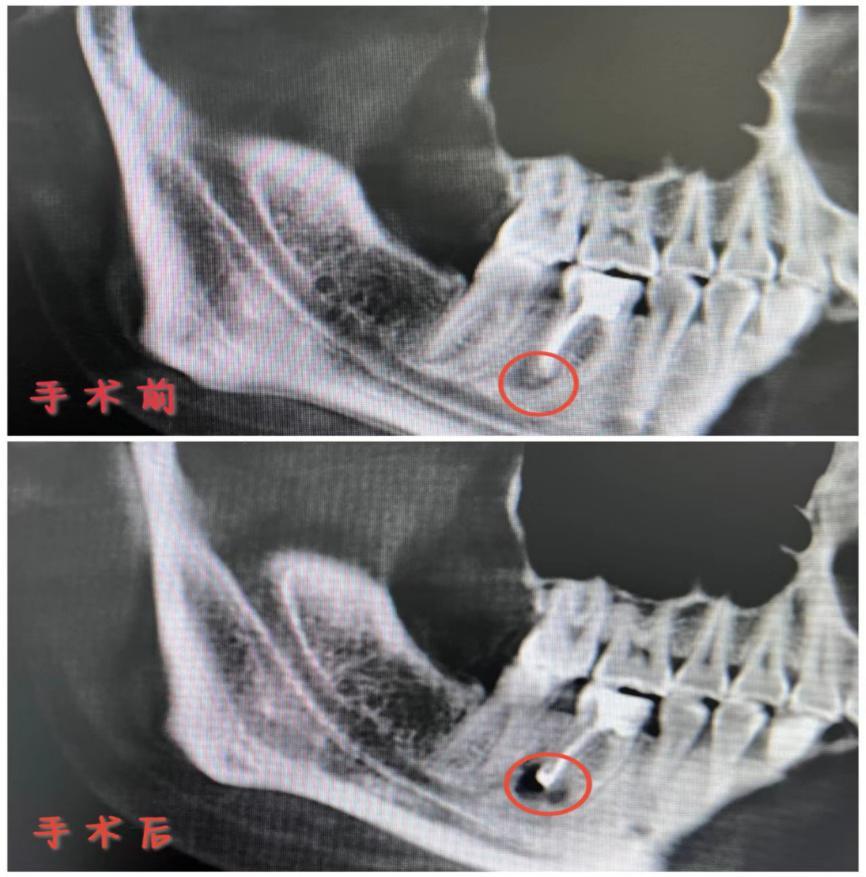

在高清显微镜的加持下,祁医生对莎莎的这颗牙进行了根尖手术,还将根尖周围囊肿进行了摘除以及彻底的清理,最后又进行了高难度的根尖倒充填治疗。

手术结束后CT复查结果显示,莎莎的治疗是很成功的,接下来只需要好好恢复一段时间,莎莎的这颗疼了10年的牙就终于“安生”了。距离此次治疗已经过去两周有余,在这期间,祁医生也进行了两次口腔随访工作,莎莎表示,自从治疗完,牙痛再没有找过她,令她开心不已。